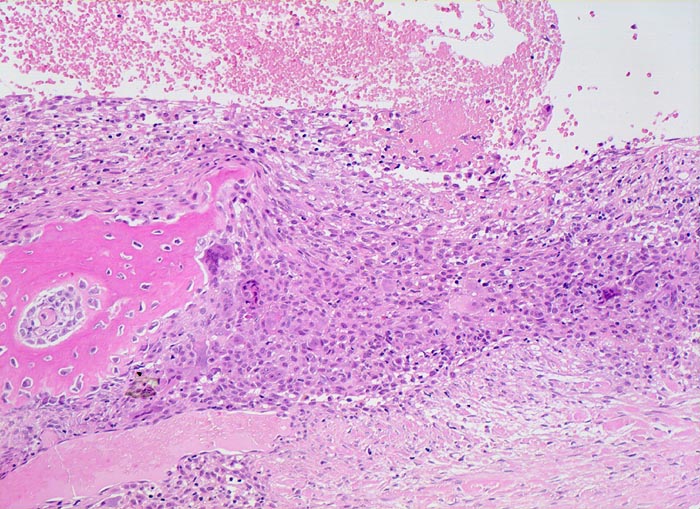

aneurysmatische Knochenzyste (AKZ)

Knochen, Fibula

Pseudozystischer Hohlraum ohne Epithelauskleidung gefüllt mit Blut. Die Pseuozystenwand enthält Riesenzellen und mononukleäre Zellen angrenzend an zellarmes kollagenes Bindegewebe. Daneben sieht man neugebildeten Faserknochen.

Lokalisierte Schmerzen und Schwellung in der proximalen Fibula. Im Röntgenbild ist eine Osteolyse erkennbar, die die betroffene Fibula auftreibt. Die Cortikalis über der Osteolyse ist hauchdünn.

Histologie

100